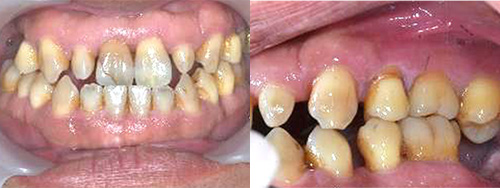

症例2. 矯正治療を含めた咬合治療

| 術前 |

|---|

![]() |

年齢:33歳

主訴:前歯の黒ずみがきになる。奥歯に穴が開いている気がする。

初診時の診断と治療方針

医療面接、レントゲンや写真より、歯並びの問題と将来的に噛み合わせから顎関節症状がでてくる恐れがあると診断できました。そのため、矯正治療を含めた咬合治療をしていくことになりました。